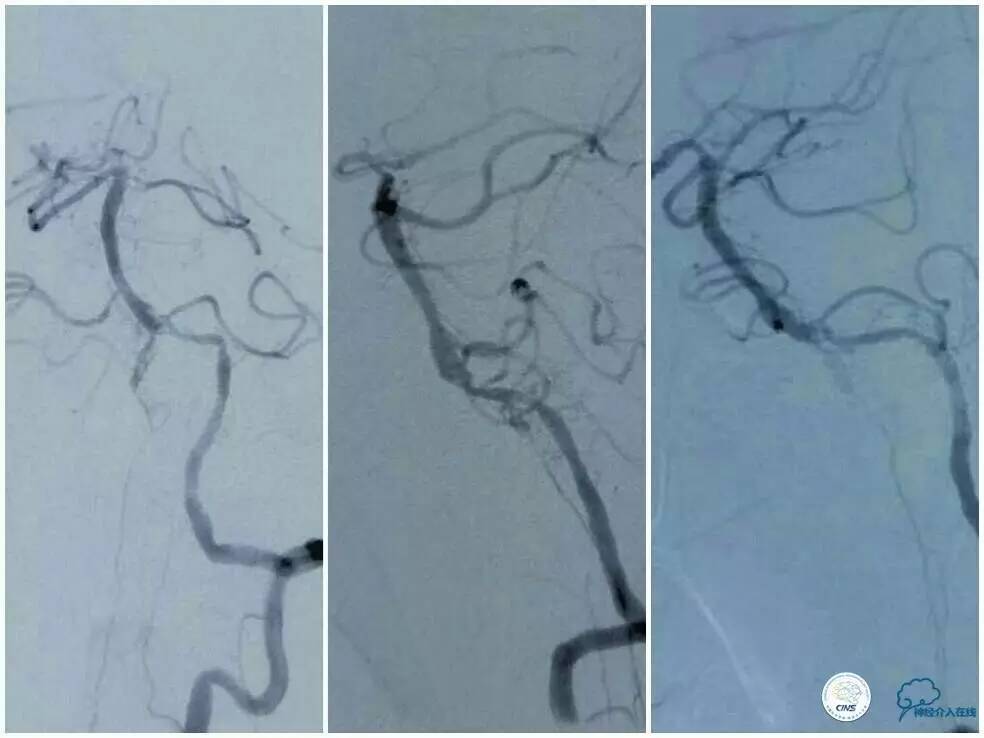

当地DSA提示:左椎动脉末端与基底动脉汇合处重度狭窄,右椎动脉经脊髓前动脉顺向和基底动脉逆向血流显影(图4);左后交通动脉开放,基底动脉尖和左大脑后动脉经其显影(图5);右颈内动脉后交通段及右大脑中动脉M1段动脉瘤(图6),为进一步诊疗而来我科。

图4

图5

微导丝到位后,原想跟进微导管(Echelon 10)行微导管造影证实在真腔,但因微导管无法越过病变而作罢。将微导丝后接Dockling延长导丝后撤出微管,依次送入Gateway1.5 mm x 9 mm,2.0 mm x 9 mm球囊预扩后,放置Winspan 3.5 mm x 15 mm支架(图9)。术后前向血流明显改善,残余狭窄约15%(图9)。

图9